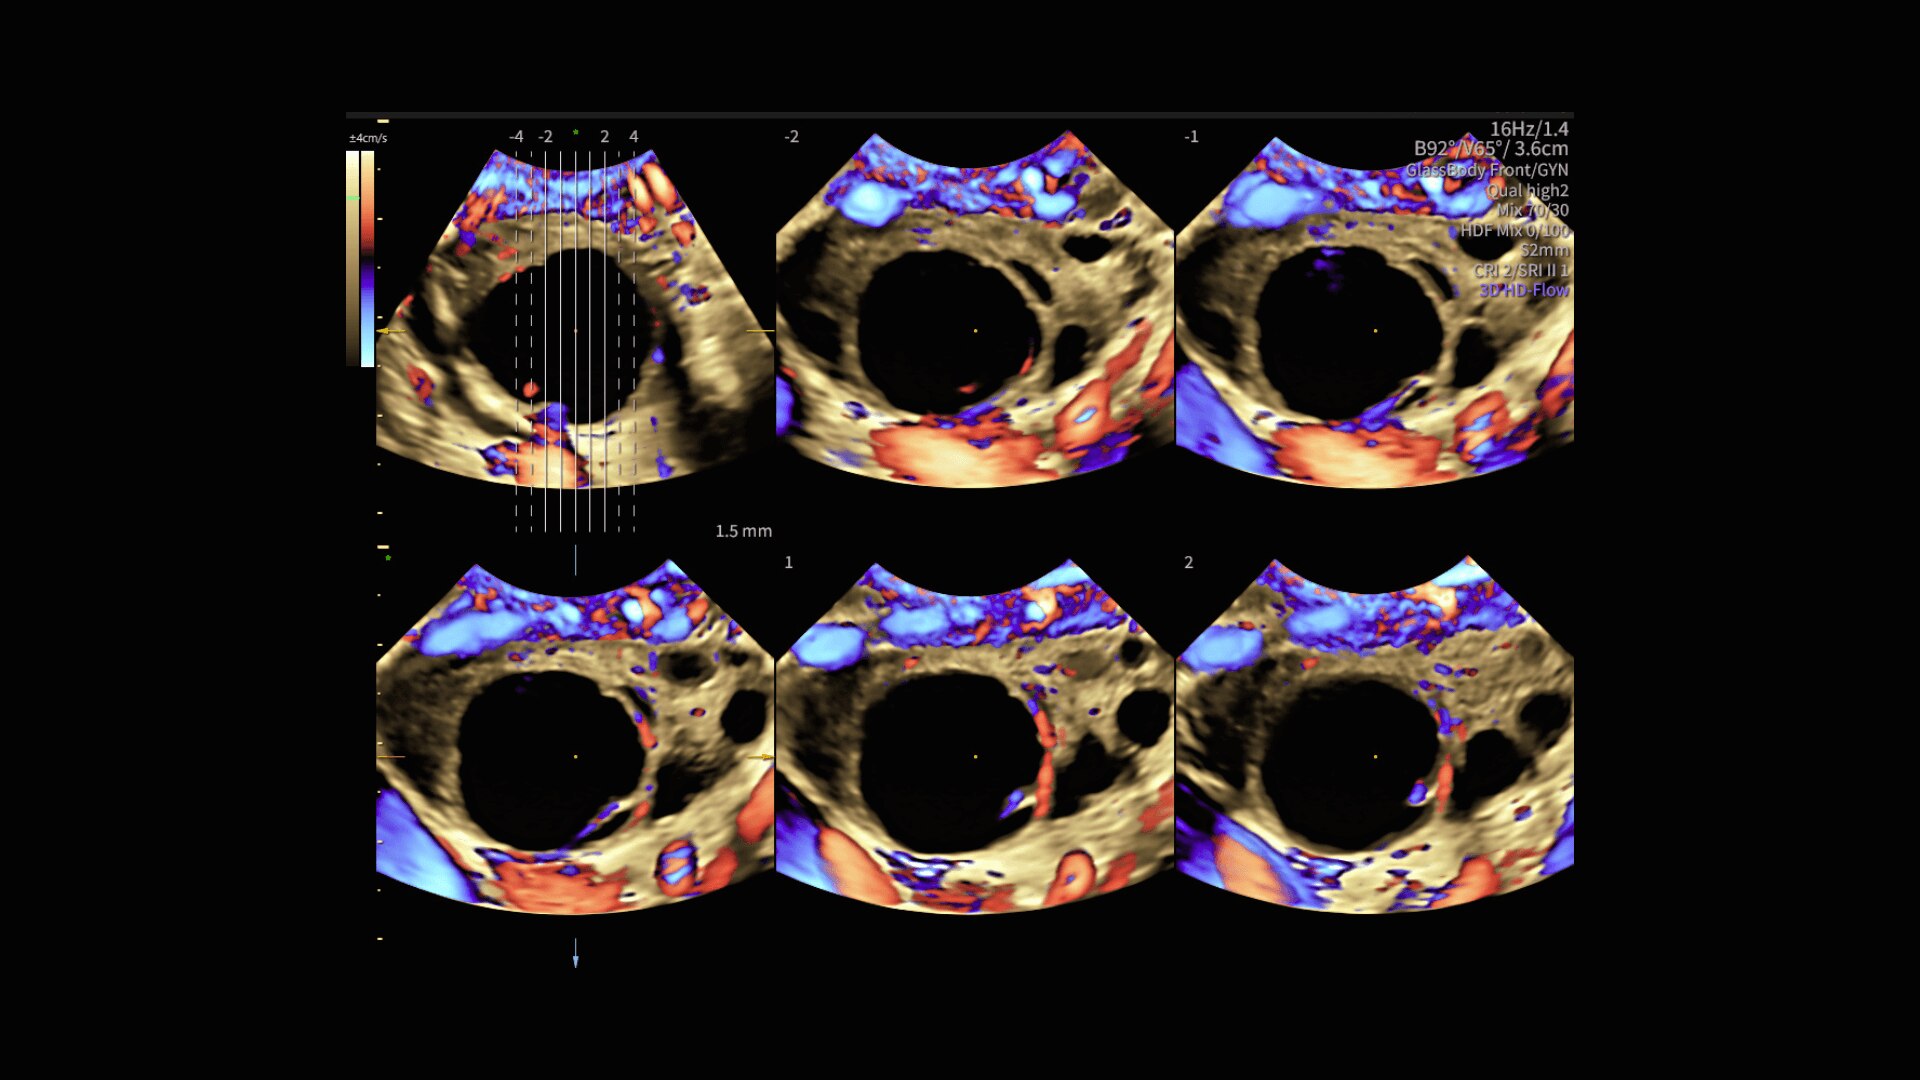

Radiantflow™

Fast, easy 3D-like blood flow visualization

Radiantflow delivers exceptionally sensitive, next level color Doppler for easy fast visualization of blood flow revealing even the tiniest vessels.